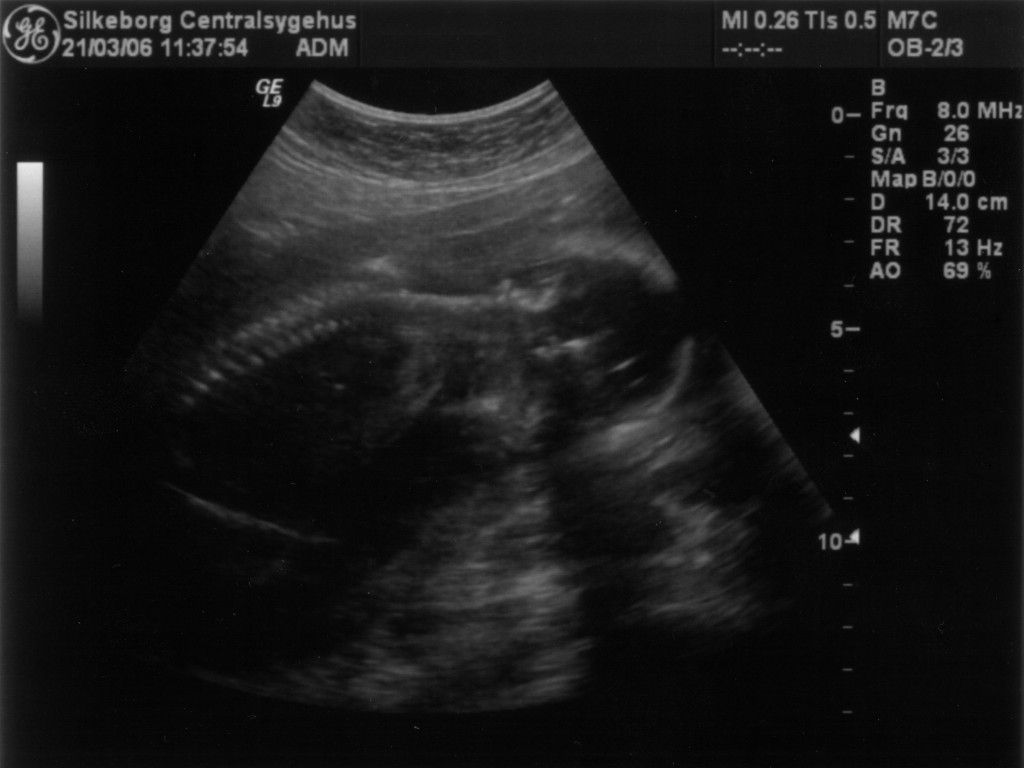

Ultralydsskanning den 21. marts 2006

Vi har i dag været på Silkeborg Centralsygehus, hvor Stine skal føde. Stine og baby blev skannet og alt var næsten som det skulle være. De var meget i tvivl om, hvorvidt der var en hjertefejl på barnet. Jordemoderen som foretig skanningen ville gerne have en overlæge til at vurdere billederne, men den eneste kvalificerede var i gang med en operation mens vi var der. Aftalen blev at de ville ringe til os, når overlægen havde set billederne. Da de ringede tilbage var deres svar at vi skal til Skejby for at få dem til at vurdere babys hjerte. Vi blev sat til at skulle skannes alleredde i morgen, da de mente at det ville være uansvarligt at lade os gå med den usikkerhed de havde skabt i flere dage. Tak! Det blev usikkerheden nu ikke mindre af... Ud over den mulige hjertefejl, kunne de også konstatere at baby er en pige. Du kan se de billeder vi fik fra skanningen herunder.